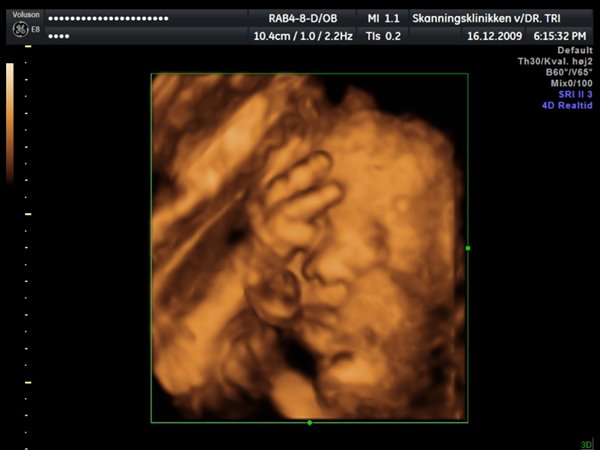

Ja, så var vi til 3D scanning med Ida igår. Og hvad kan jeg sige andet end hun er en meget træt pige

Jeg tror vi talte hun gabte mellem 10 og 11 gange under hele scanningen. Derudover havde hun meget travl med at gemme sig bag sine hænder som hun hele tiden åbnede og lukkede så det så ud som om hun vinkede

Billederne blev ikke så gode som jeg havde håbet, for lige som sin bror ligger hun meget tæt på moderkagen og med navlestregnen forand hovedet. Men de er ok, vi kan da se at hun ser sund og rask ud og at hun trives derinde.

Vedhæftede fotos (klik for at se i fuld størrelse)